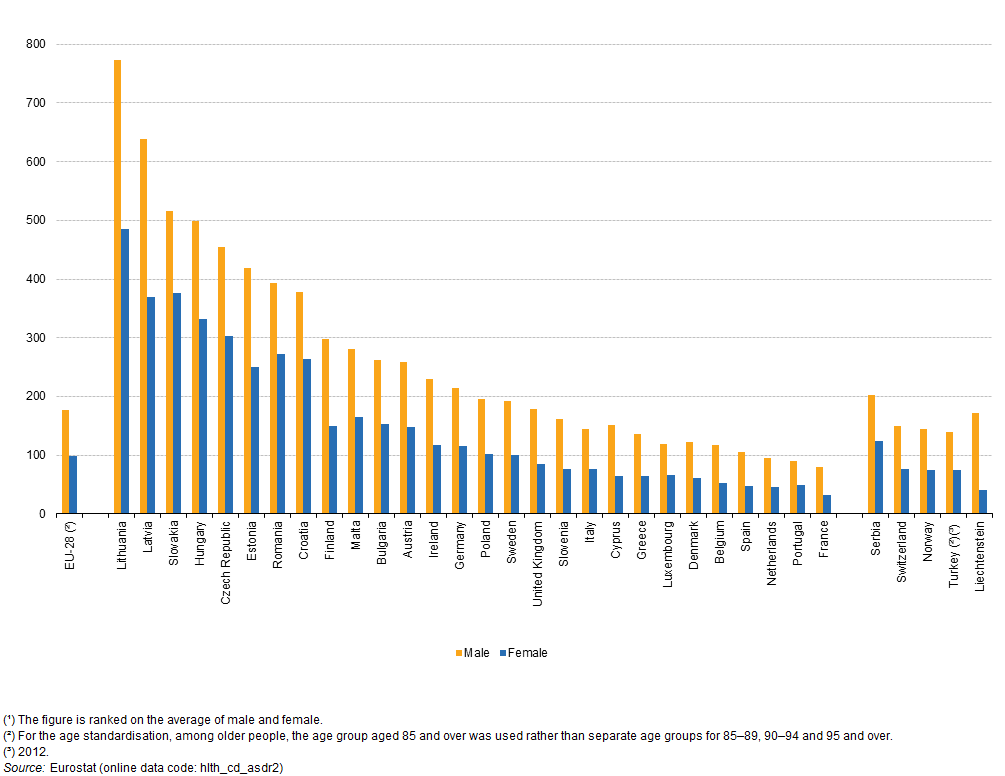

Poďme sa pozrieť ešte na ďalšie tri štatistiky. V roku 2000 spôsobilo ochorenie obehovej sústavy v SR celkovo 53,4% všetkých úmrtí, najviac ICHS - 45,5% mužov a 35,8% žien. Dobrou správou ale je, že si ľudia začínajú uvedomovať riziko týchto ochorení a prevenciou sa im snaží predísť. Dokazuje to štatistika z roku 2013, kedy na ochorenia obehovej sústavy zomrelo "len" 670 ľudí na 100 000 obyvateľov a na ischemickú chorobu srdca 364 ľudí na 100 000 obyvateľov. Dokazuje to ale aj lepšiu lekársku starostlivosť, možnosť dopravenia sa do nemocnice včas a modernejšie metódy a postupy v lekárstve.

Za rok 2015 bola štatistika nasledujúca:

Choroby obehovej sústavy: Takmer 51 000 mŕtvych

Ischemická choroba srdca: Takmer 21 200 mŕtvych

Na grafe ale vidíme, že aj keď sa u nás počet mŕtvych na ischemickú chorobu srdca znížil, aj tak sme v Európskej únii obsadili tretie miesto, a to nie je práve povzbudzujúca informácia. Žltá stupnica navyše ukazuje početnosť úmrtí u mužov, modrá potom u žien. Môžete si všimnúť, že najmenšiu početnosť možno nájsť u štátov ako Francúzsko, Portugalsko, Holandsko, Španielsko, Belgicko... Všetky tvoria prímorské štáty, tak kde asi hlavne bude zakopaný pes?